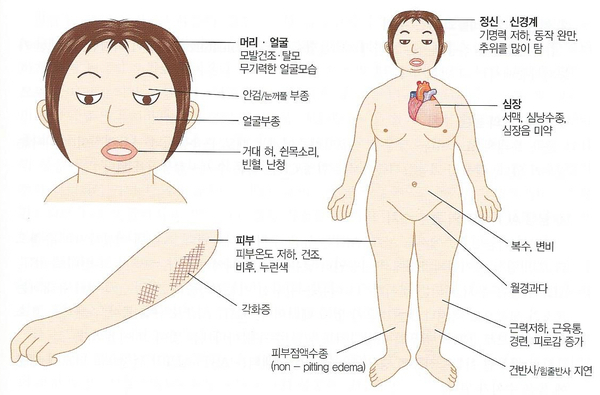

갑상선 기능 저하증의 증상, 갑상선 기능 저하증의 증상은 갑상선 기능 항진증의 대표 질환인 그레이브스병의 증상과 정반대로 나타납니다.

- 열생산이 저하되어 추위에 약합니다.2. 땀이 줄고 건조가 나타납니다.3. 모발이 건조하여 빠지기 쉽고 눈썹, 액모, 음모의 모량이 적어집니다.4. 육체적, 정신적 활동성이 느려지고 기억력도 떨어집니다.5. 식욕부진이 나타나고 장운동이 떨어져 변비가 빈발합니다.6. 점액수종이 눈꺼풀에 나타나 혀나 인두 점막에 생기면 거대 혀나 마른 목소리를 가져옵니다. 점액수종은 일반 부종과 달리 눌러도 흔적이 남지 않고 단백질의 이화가 이루어지지 않아 피하조직에 지긋지긋하다.당이 침착되어 발생합니다.7. 서맥이 나타나고 심막내강에 액체가 저장되면서 심음이 약해지고 심전도 상에서 낮은 전위가 나타납니다. 심박수도 저하되어 혈압은 정상 또는 저하됩니다.8. 고혈압이 될 수도 있습니다. 갑상선 기능 저하증이 진행되면 뮤코다 당류가 침착되고 결국 고콜레스테롤혈증을 동반하여 동맥경화가 촉진되어 고혈압 및 관상동맥경화가 유발됩니다.9. 여성에서 초기에는 월경과다를 일으키는 경우가 많으며 후기가 되면 무월경이 됩니다.10. 여성에서는 젖 분비가 보이는 경우가 있습니다. 저하된 T3, T4에 자극받아 시상하부에서 TRH 분비가 항진되는데 TRH는 TSH뿐만 아니라 프롤락틴(유분비 호르몬) 분비도 항진시키기 때문입니다.